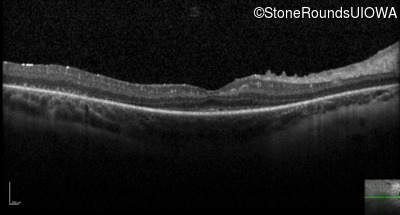

Optical Coherence Tomography - Right - 20/40 -2

Exemplar / OCT Stack

Optical Coherence Tomography - Right - 20/70